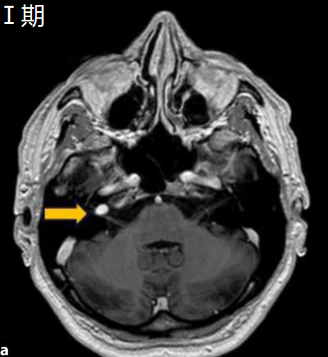

- Ⅰ期:内听道期

肿瘤局限于内听道内,仅有听神经受损表现,除耳鸣、听力减退、眩晕和眼球震颤外,无其他临床症状。